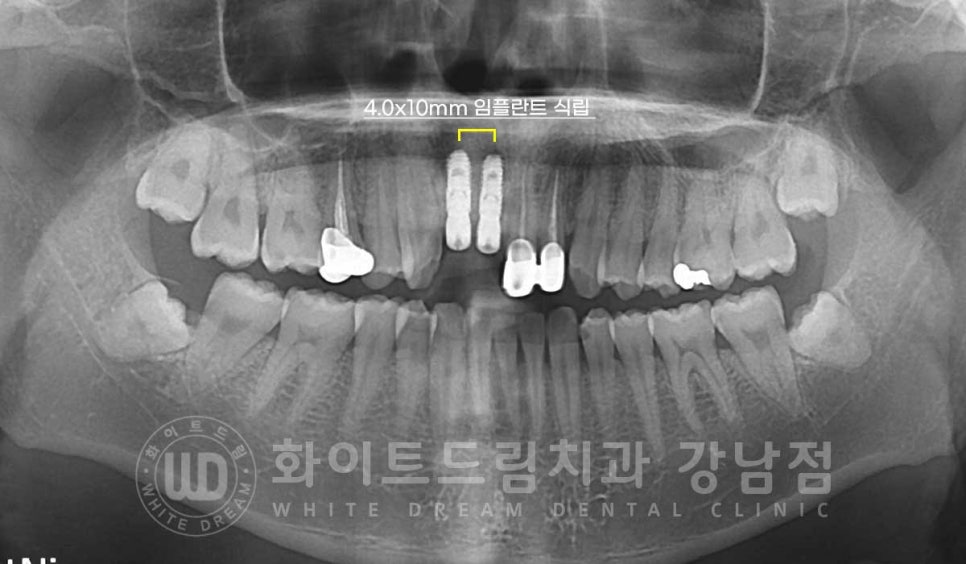

앞니는 보통 어금니 부위보다 골폭이 좁아 직경이 얇은 임플란트를 많이 식립합니다.

보통 어금니는 직경 5mm 정도의 임플란트를 식립하는데

앞니는 남아있는 잇몸뼈의 양에 따라 보통 4-3mm 사이의 임플란트를 식립하게 됩니다.

환자분은 다행히 골이식으로 모자란 잇몸뼈를 커버할 수 있을 것으로 판단되어

직경 4mm의 임플란트를 2대 식립하기로 했습니다.

환자분은 수술 당일 골이식 + 임플란트 식립을 함께 진행하면서

2차 수술까지 한 번에 진행을 했습니다.

▲ 앞니 임플란트 수술일자 : 23.05.04